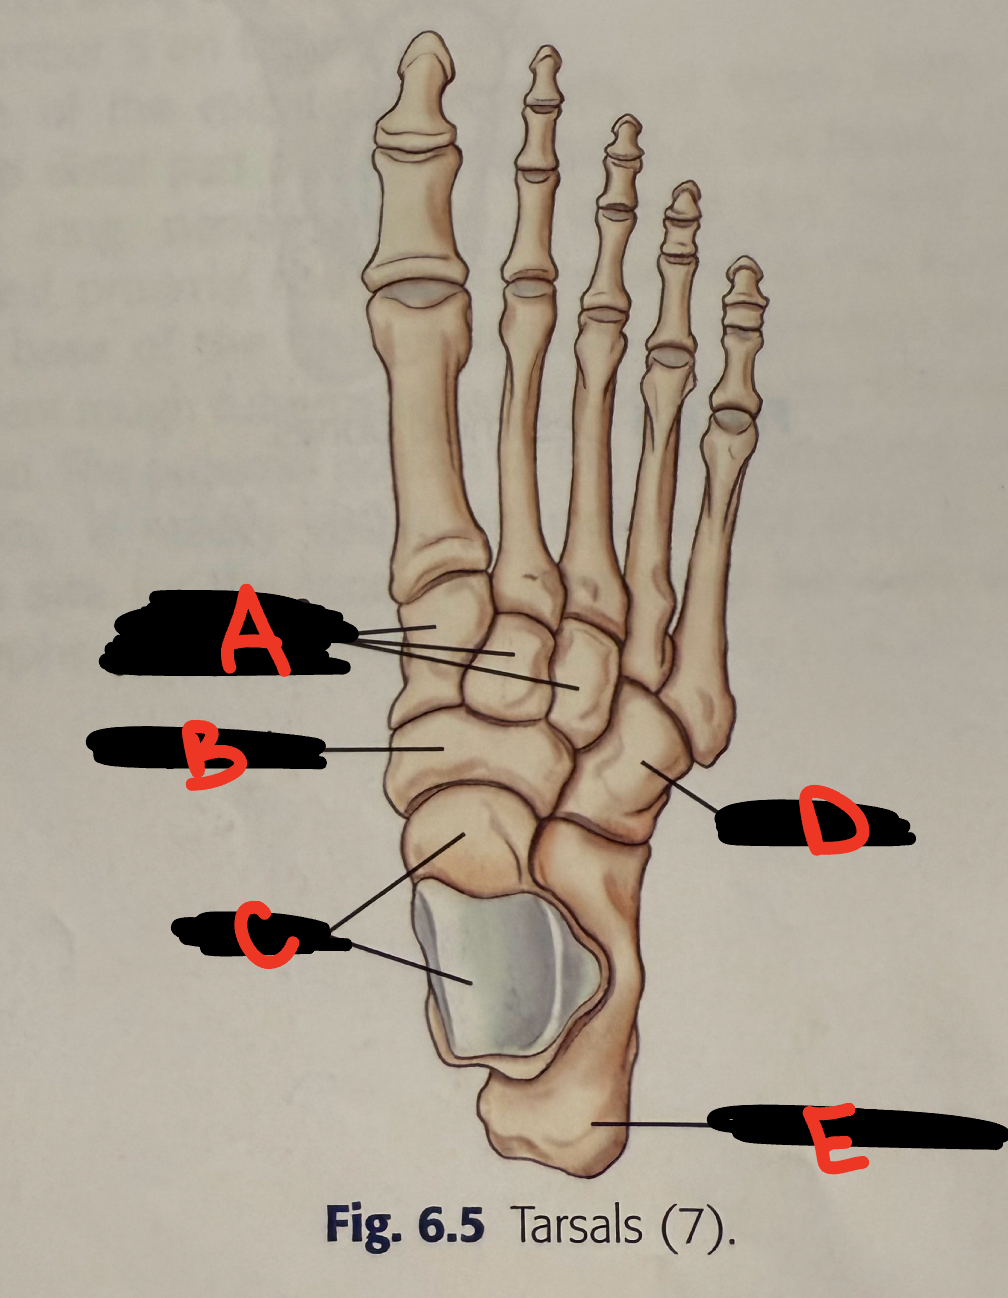

anterior tubercle

8

New cards

<p>C</p>

C